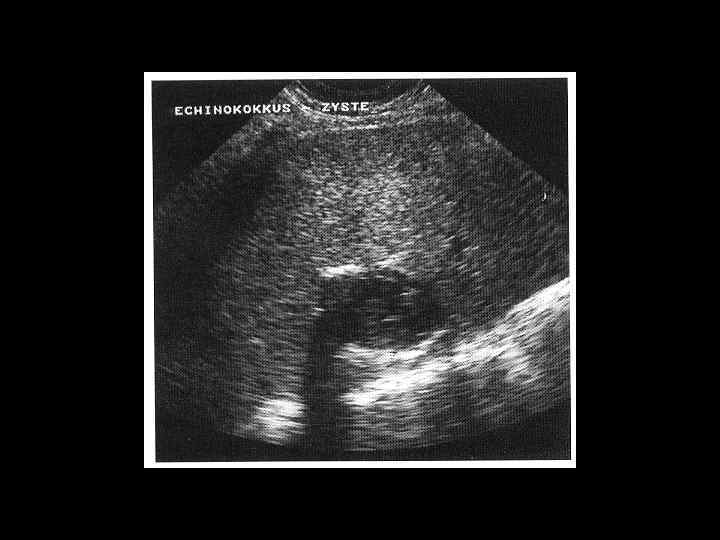

АКТУАЛЬНЫЕ ВОПРОСЫ РЕНТГЕНОЛОГИИ ЛУЧЕВАЯ ДИАГНОСТИКА ОЧАГОВЫХ ПОРАЖЕНИЙ ПЕЧЕНИ ЭХИНОКОККОВЫЕ КИСТЫ УЗИ: краевые кольцевидные обызвествления КТ: низкоплотностные образования с перегородками и четкими контурами МРТ: образования дающие гиперинтенсивный сигнал на Т 2 взвешенных изображениях